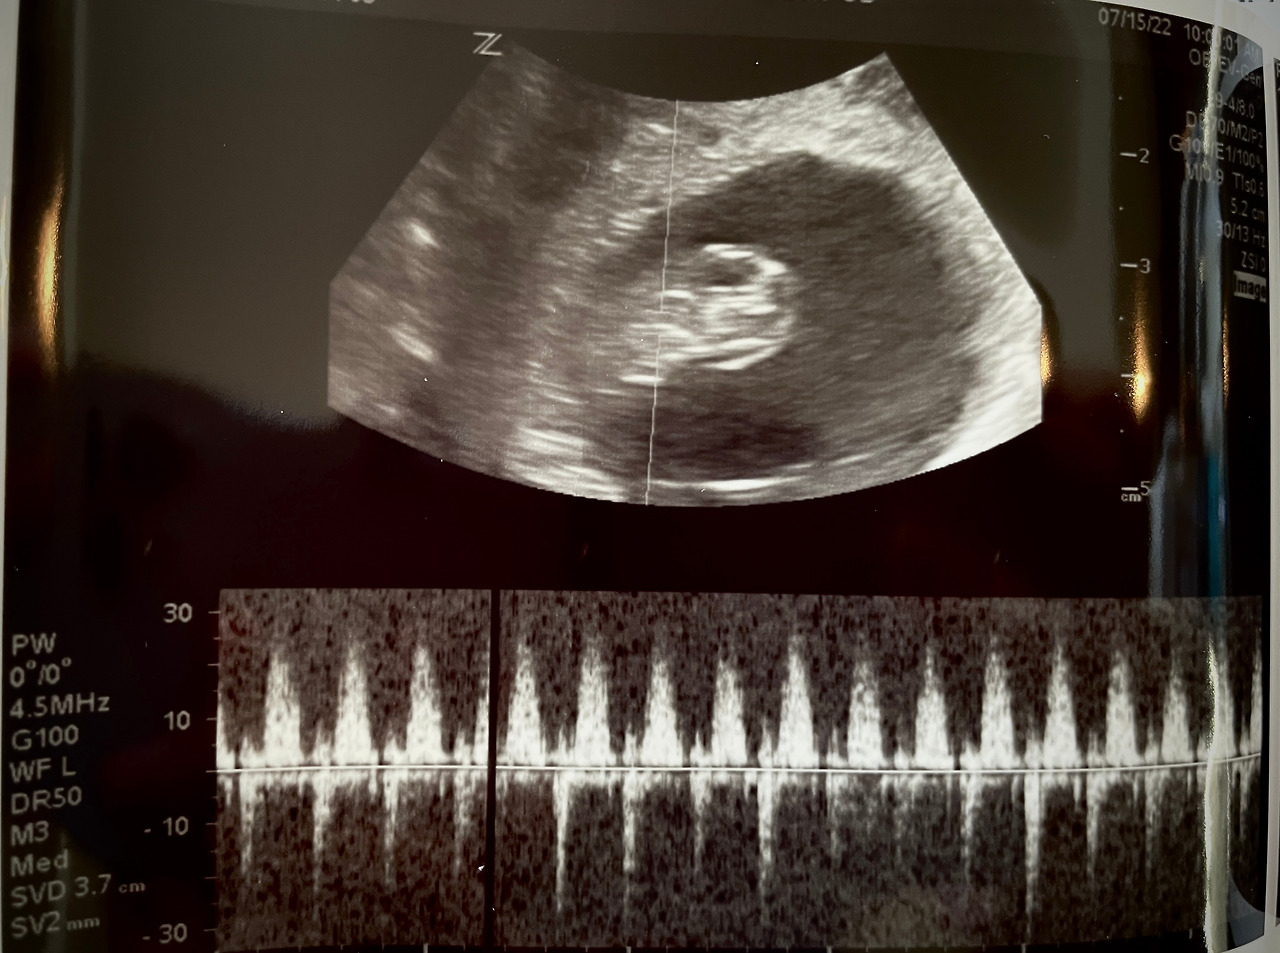

임신 초기 초음파

임신 초기 이야기는 우리 세상이의 8주차, 12주차 초음파 사진과 영상으로 마무리 :)

8주차와 12주차 - 하리보 같이 꼬물거리던 세상이

8주차 - 세상이 심장소리를 처음 들은 날